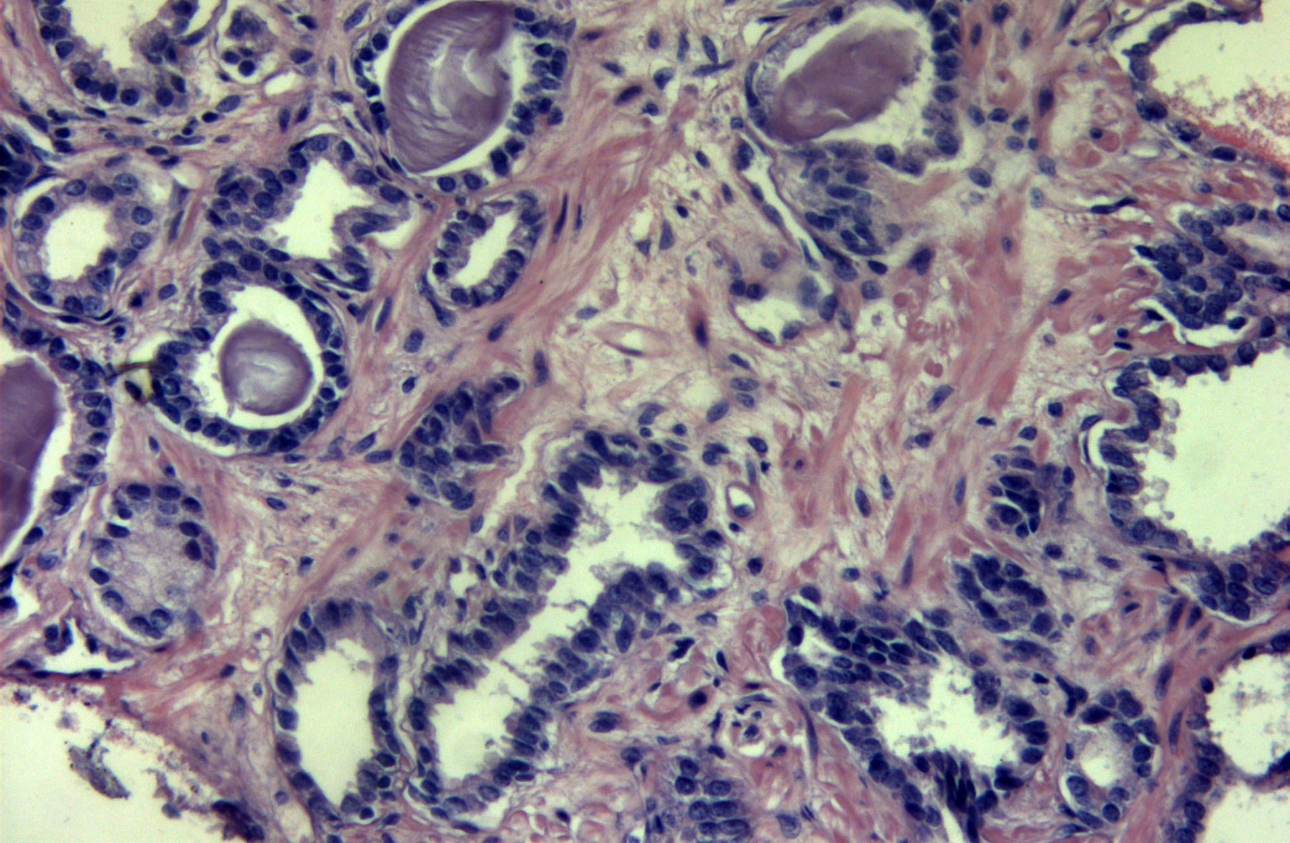

Histological examination: in a column of tissue from the area of interest, the growth of acinar adenocarcinoma is 7 points according to Gleason (3 + 4). Histological result of focal formation of the peripheral zone on the right, acinar adenocarcinoma is represented by light tumor acinuses that do not have a basal cell layer. (Fig. 6).

Classical ultrasound signs of prostate cancer are considered to be hypoechoic, hypervascular formation in the peripheral zone with a fuzzy contour [1]. These signs are characterized by low specificity, since similar changes can occur with various benign changes [2]. In this regard, multiparametric ultrasound is necessary to provide additional diagnostic information. Strain elastography can provide a map of the tissue stiffness in a given region of interest. While malignant lesions tend to be stiffer than normal tissue, this is not always so, as seen in this particular case where strain ratios did not indicate significant change in stiffness between the focal lesion and the surrounding intact tissue. CEUS can provide more detail regarding tissue vascularity. In this case, CEUS examination confirmed pathological vascularization within the focal lesion seen on B mode imaging, not just by qualitative signs, but also by quantitative parameters.